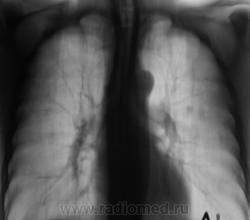

Рентгенограмма.

С двух сторон в верхних долях очаги. На вскидку tbs. А что с клиникой, анализами, анамнез.

Пациент взят на контроль после прохождения профилактической флюорографии. Жалоб нет, соответственно нет и анамнеза. В 2009 флюорографию не проходил, в 2008 году - флюорограмма- "голубая норма"

Двусторонний очаговый туберкулез.

В s 1 -2 и глубоких отделах s6судя по срезам очаги,справа с включениями кальция,на фоне фоброзно измененного легочного рисунка

Скорее диссеминирмванный так как пораженно более 2-х сегментов.

Такое ощущение, что он свой ТБС уже пережил, возможно на ногах. Иногда фтизиатры пользуются термином - самоизлеченный ТБС ( возможно чуть по другому). А вот те тенюшки в левом легком - это то, что может вырасти в дальнейшем в какое-нибудь деонтологическое заболевание. Цепляться ли за них сейчас? Через год будет поздно. Мы такое уже проходили. И что-же делать?

Коллеги, кто может, укажите стрелками на обзорной рентгенограмме очаги. Я не вижу.

Согласен, нежные дела и проглядеть легче легкого по бзорке, тем более там где зачастую не ждешь его)))